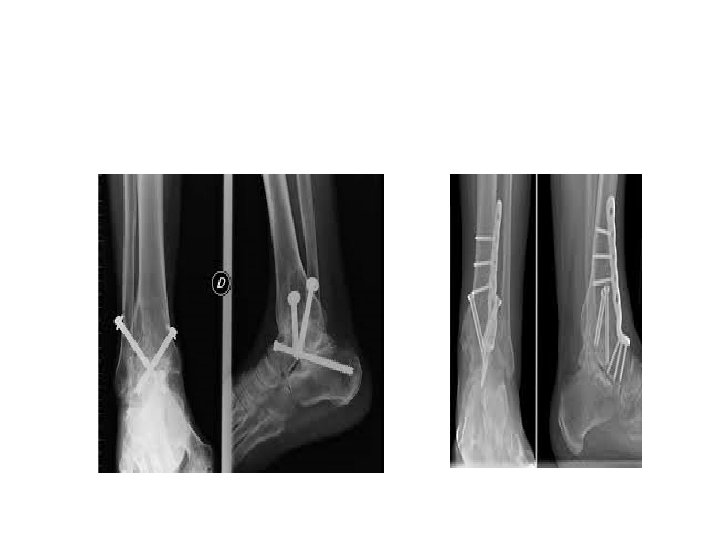

CONTINUED • AFTER PREPARATION , COMPRESSION OF THE JOINT SURFACES WITH INTERNAL FIXATOR • 2 CANNULATED SCREWS PLACED ACROSS THE TIBIA INTO THE TALUS • 1 ST-LATERAL ASPECT OF TIBIA INTO THE NECK OF THE TALUS • 2 ND-MEDIAL MALLEOLUS INTO THE LATERAL ASPECT OF TALUS • POST OPERATIVELY-5 WEEKS NON WEIGHT BEARING

OPEN ARTHRODESIS • TWO INCISION TRANSFIBULAR EXPOSURE • CAN USED FOR ANY PATIENTS • USEFUL FOR PATIENTS WITH SEVERE ANKLE JOINT DEFORMITY • BETTER VISUALIZATION, IMPROVED ASSESS FOR BONE RECESSION, CORRECTION OF DEFORMITY & SCREW PLACEMENT

STUDY BY OGILVIE-HARRIS • 3 CROSSED SCREWS GENERATED SIGNIFICANTLY MORE COMPRESSION & RESISTANCE TO TORQUE ACROSS THE ARTHRODESIS SITE THAN 2 SCREWS • BETTER COMPRESSION WHEN LATERAL SCREW PLACED FIRST • ONE LATERALLY, ONE MEDIALLY, ONE ANTERIORLYFROM TIBIA TO TALUS

TIBIOTALAR ARTHRODESIS WITH SCREW FIXATION • MANN ET AL • INCISION-10 CM PROXIMAL TO THE TIP OF FIBULA AND CARRYING IT DOWN ALONG THE FIBULAR SHAFT. DISTALLY 10 CM TOWARS THE BASE OF FOURTH METATARSAL • OSTEOTOMIZE THE FIBULA APPROX 2 CM PROXIMAL TO ANKLE JOINT